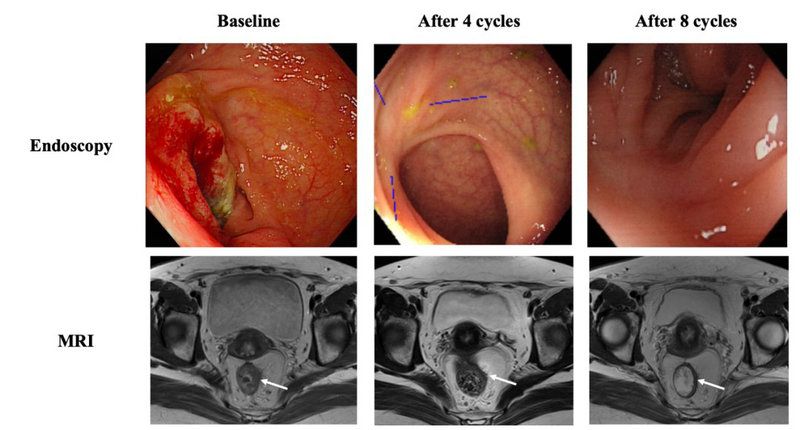

一例患者治療前后的腸鏡及MRI圖像,可見腫物已完全消退